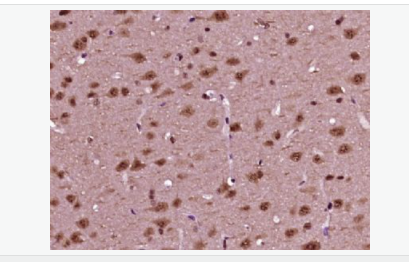

交叉反應:Human,Mouse,Rat(predicted:Pig,Cow,Sheep) 推薦應用:WB,IHC-P,IHC-F,ICC,IF,ELISA

| 產品應用 | WB=1:500-2000 ELISA=1:5000-10000 IHC-P=1:100-500 IHC-F=1:100-500 ICC=1:100-500 IF=1:100-500 (石蠟切片需做抗原修復) not yet tested in other applications. optimal dilutions/concentrations should be determined by the end user. |

| 細胞定位 | 細胞核 細胞漿 |

| 產品介紹 | This gene encodes a member of the NeuroD family of basic helix-loop-helix (bHLH) transcription factors. The protein forms heterodimers with other bHLH proteins and activates transcription of genes that contain a specific DNA sequence known as the E-box. It regulates expression of the insulin gene, and mutations in this gene result in type II diabetes mellitus. [provided by RefSeq, Jul 2008] Function: Differentiation factor required for dendrite morphogenesis and maintenance in the cerebellar cortex. Transcriptional activator. Binds to the insulin gene E-box. Subcellular Location: Cytoplasm. Nucleus. Post-translational modifications: Phosphorylated. In islet cells, phosphorylated on Ser-274 upon glucose stimulation; which may be required for nuclear localization. In activated neurons, phosphorylated on Ser-335; which promotes dendritic growth. DISEASE: Defects in NEUROD1 are the cause of maturity-onset diabetes of the young type 6 (MODY6) [MIM:606394]. MODY is a form of diabetes that is characterized by an autosomal dominant mode of inheritance, onset in childhood or early adulthood (usually before 25 years of age), a primary defect in insulin secretion and frequent insulin-independence at the beginning of the disease. Similarity: Contains 1 basic helix-loop-helix (bHLH) domain. SWISS: Q13562 Gene ID: 4760 Database links: Entrez Gene: 4760 Human Entrez Gene: 18012 Mouse Omim: 601724 Human SwissProt: Q13562 Human SwissProt: Q60867 Mouse Unigene: 574626 Human Unigene: 709709 Human Unigene: 4636 Mouse Unigene: 44289 Rat Important Note: This product as supplied is intended for research use only, not for use in human, therapeutic or diagnostic applications. |